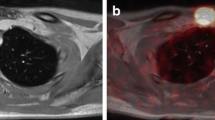

Many clinical studies have shown the superiority of 124I PET/CT versus 131I conventional imaging (planar images and/or SPECT/CT), which is attributable to the possibility of combining morphological imaging and highly specific functional imaging, avoiding most of the known pitfalls of 131I scanning. This approach could also lead to improved clinical decision-making. See Figs. 1 and 2.

124I PET/MRI may also be a useful instrument: in a study of 33 high-risk DTC patients, Nagarajah et al. [56] intra-individually and prospectively compared the lesion detection ability of 124I PET alone and 124I PET used in combination with CT and MRI, considering their ability to characterize a lesion as thyroid remnant tissue or lymph node metastasis, and the consequences of higher detectability on lesion dosimetry. They found that MRI detected more morphological correlates to PET foci than CT did, and 65 % of these lesions were <10 mm in diameter. They concluded that PET/MRI is superior to PET/CT in pre-therapeutic imaging, particularly in lesions measuring <10 mm in diameter, resulting in more precise and individually tailored 124I dosimetry.